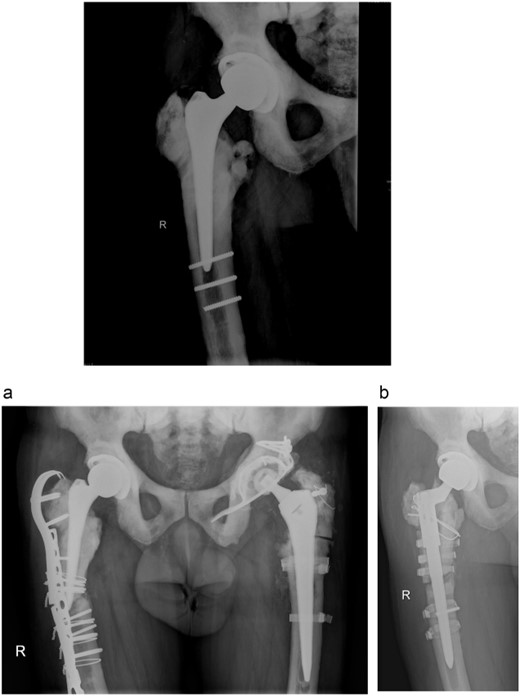

A 73-year-old man showed himself to our hospital in 1989, complaining of left hip pain. X-ray imaging revealed advanced osteoarthritis of the left hip as well as skeletal abnormalities pathognomonic for osteopetrosis. Following earlier intertrochanteric osteotomies carried out elsewhere, there was osteosynthetic material present in the right femur. A cementless isoelastic total hip arthroplasty (THA) was performed (Fig. 1). The greater trochanter was fractured and repaired with screws and cerclages.

Isoelastic uncemented hip arthroplasty. Broken trochanteric part was fixed with cerclage wires and screws.

In 2011, a cementless THA of the right hip was done for the osteoarthritis. Three residual broken screws were present in the distal diaphysis from previous surgeries and were left in place (Fig. 3).

Anteroposterior radiograph of the right hip after THA with three broken residual screws in the distal diaphysis. (a) Anteroposterior hip radiograph with broken lateral plate. (b) Anteroposterior radiograph of the right hip after exchanging the femoral stem.

In 2013, the patient suffered a spontaneous Vancouver B2 periprosthetic fracture of the right THA. Osteosynthesis with a locking plate with screws and cerclages was done. Three months after the surgery, the plate broke and was exchanged with addition of an anterior plate and autologous spongioplasty. However, osteosynthesis failed 8 months later and the firmly ingrown femoral component was revised (Fig. 3a). Proximal femoral osteotomy resulted in several broken fragments. During removal of the broken screws, three sets of removal instruments were destroyed. A cementless revision modular stem was inserted and bone fragments fixed with cerclage wires and titanium tapes (Fig. 3b). Surgery took 6 h and he received six units of blood. Microbiological tissue samples were negative.